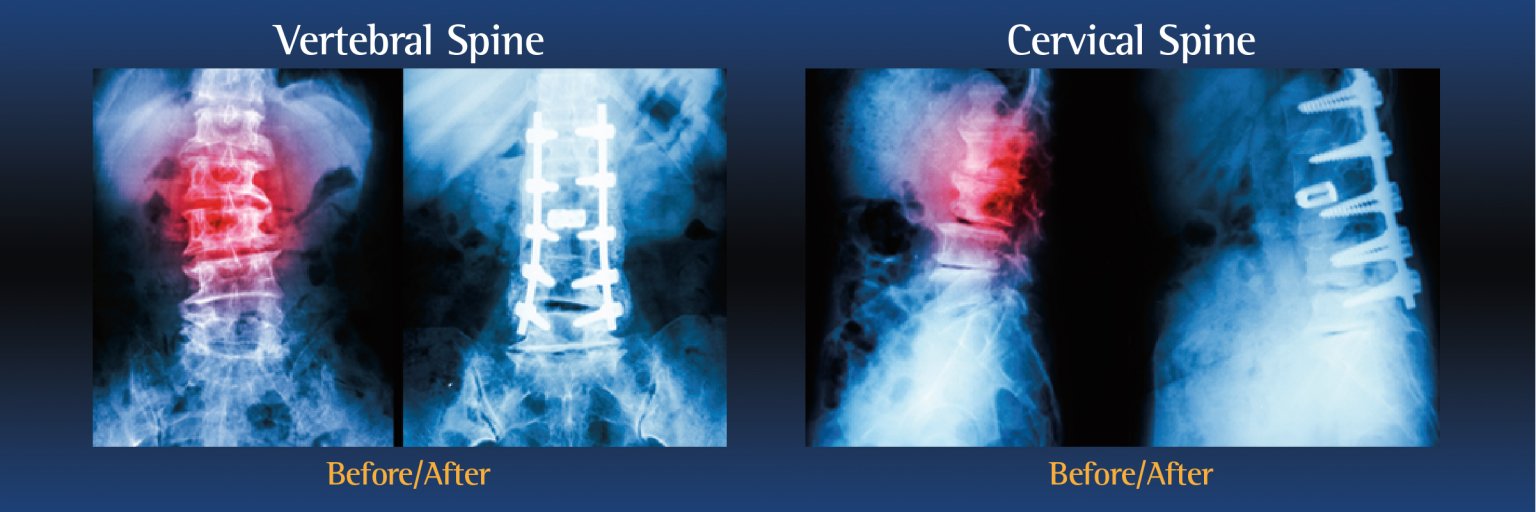

Types of spinal fusion surgery

There are several types of spinal fusion surgery. The type of procedure performed will depend on the patient’s individual condition, as well as the location of the pain:

- Cervical Fusion is performed on the neck

- Lumbar Fusion is performed on the lower back

During the operation, an incision is made in the neck, back or abdomen. Bone, debris, bone growths, lamina, and/or the damaged vertebral disc may be cleared from the spine, creating more space and relieving pressure on the spinal nerves. The surgeon will then take the proper steps to correct the patient’s specific problem.

Bone grafts may then be placed in the space or along the side of the spine. If additional support is needed, metal hardware (including pins or screws), may be used to steady the spine as it fuses. The incision is closed to finalize the surgery.

The grafts will grow into solid bone, fusing together the vertebrae. Patients may have to wear a back brace post-surgery, which will support your spine and keep the vertebrae from moving as the grafts fuse together.